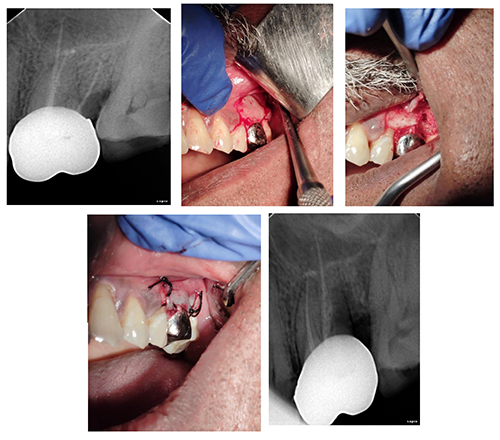

Radisectomy

One diseased root of Upper Molar is removed & rest part is saved.